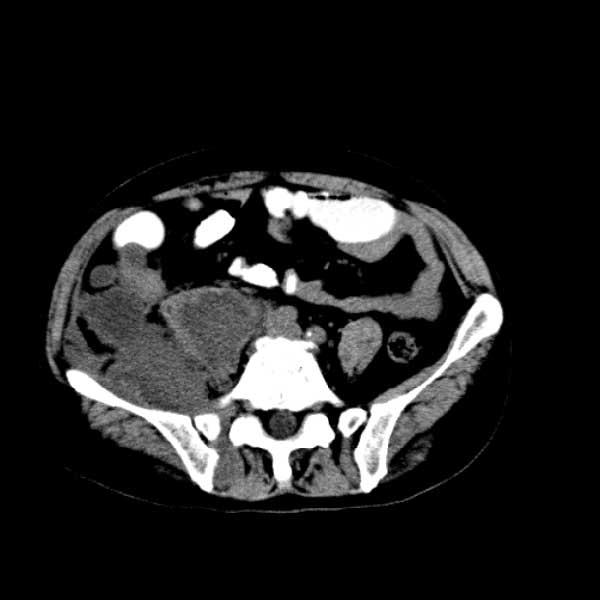

标题: CT13513:男 71 腹部疼痛20余天,近几天高热就诊,骨窗未见异 [打印本页]

考虑感染性病变可能性大,起源于阑尾?

感染,脓肿形成

考虑为化脓性阑尾炎.脓肿形成.及多肌肉累及.

考虑右侧腰大肌脓肿,向右髂窝、右腹股沟流注。

支持化脓性阑尾炎伴右髂窝脓肿、腰大肌腰方肌脓肿形成。

首先考虑化脓性阑尾炎伴腰大肌、腰方肌脓肿,不除外回盲部结核。

回盲部癌待排除。

患者肠镜检查考虑结肠癌,病理证实

患者肠镜检查考虑结肠癌,病理证实。肺部ct可见多发结节,考虑转移